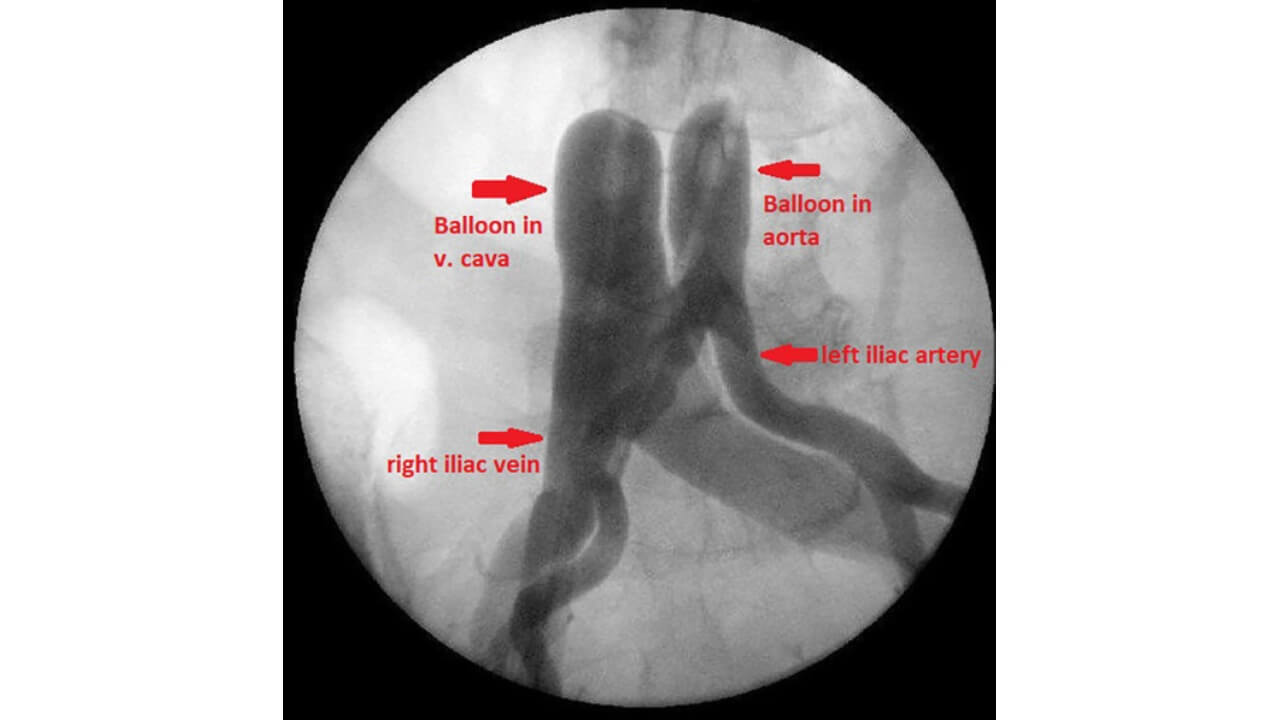

بعد تركيب القسطرة، يتم إجراء عزل إلزامي للمنطقة باستخدام بالونات خاصة. تُوضع هذه البالونات الانسدادية في الأوعية الدموية الرئيسية أعلى وأسفل المنطقة المغذية للورم. وبمجرد نفخها، تسد تدفق الدم تماماً، مُكَوّنةً مقطع إرواء مُغلق. تُتيح هذه التقنية التحكم الكامل في انتشار الدواء وتوفر أعلى جرعات موضعية ممكنة من العلاج الكيميائي.

يُعدّ العزل بالبالون عنصراً أساسياً في العلاج الكيميائي الإقليمي، إذ يسمح بإيصال جرعات عالية من الدواء دون خطر دخول كميات زائدة إلى الدورة الدموية الجهازية. أثناء الإجراء، يُراقب أخصائيو الأشعة التداخلية باستمرار الضغط داخل مقطع الإرواء، ودرجة الانسداد، والموضع الصحيح لأجهزة الانسداد. وهذا يضمن دوران دواء العلاج الكيميائي ضمن منطقة محددة فقط (مُستهدِفاً الخلايا السرطانية مع تقليل التأثير على الخلايا السليمة).

الإرواء البطني ناقص الأكسجة مع إيقاف التدفق (HAP) يُعدّ طريقة لعزل تجويف البطن، ويُستخدم لعلاج أورام المعدة، والبنكرياس، والقولون، والكبد، وغيرها. يتم وضع بالونات في الشريان الأبهر البطني والوريد الأجوف السفلي، مما يؤدي إلى توقف تدفق الدم من وإلى تجويف البطن تماماً لعدة دقائق. يخلق ذلك ظروفاً مثالية لتركيز العلاج الإقليمي بأقصى قدر في منطقة الورم. يتم إعطاء العلاج الكيميائي عالي التركيز عبر قسطرة منفصلة، حيث يدور الدواء فقط ضمن التجويف المعزول [13].